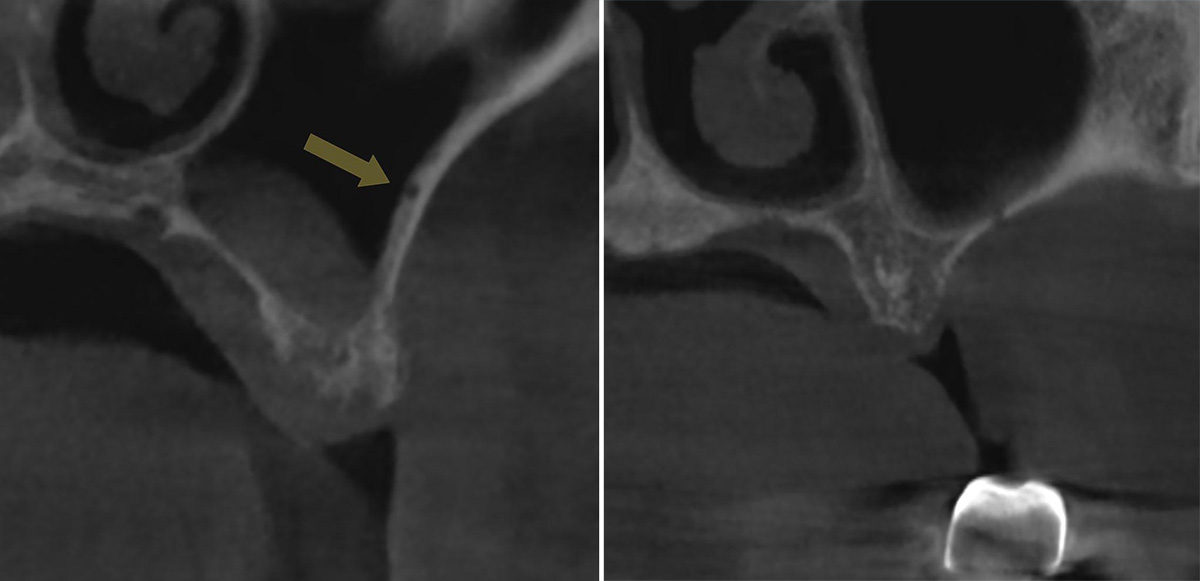

Для определения расположения ААА на КЛКТ важно выявить дискретный канал или вдавление в латеральной стенке верхнечелюстного синуса (рис 1.a, b) [2,16].

рис 1.jpg

Рисунок 1. Рентгенологические признаки альвеоло-антральной артерии на коронарном реформате КЛКТ.

a: вдавление в латеральной стенке верхнечелюстного синуса (стрелка);

b: прерывание стенки верхнечелюстного синуса.